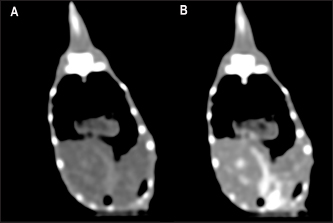

The contrast study was successfully performed in 27 out of 30 animals (15 veiled chameleons and 12 panther chameleons). However, accidental contrast extravasation occurred in three veiled chameleons and two panther chameleons, with contrast remaining adjacent to the injection site tissue. In the postcontrast study, the contrast enhancement was better observed at 1 minute than 30 seconds after contrast administration (Fig. 3). Therefore, 1-minute postcontrast images were used for the postcontrast attenuation measurements.

Fig. 3. The postcontrast CT transverse images displayed in the soft tissue window show better contrast enhancement in the hepatic section observed at 60 seconds (B) than at 30 seconds (A) after contrast administration.

The contrast enhancement was better visualized after 1 minute of the administration due to the low heart rate of these species. These results agree with the study of Nardini et al. (2014). In green iguana, the contrast medium was observed in the CVC 3 seconds after injection, but not in the aorta. Thirty-six seconds after injection the contrast was visible in the liver parenchyma, and after 600 seconds the contrast was still mildly appreciable in the liver (Nardini et al., 2014). As expected, the parenchymal organs enhanced after contrast administration. In the same way that was described for captive green iguanas (I. iguana) (Nardini et al., 2014), no side effects were observed in any animal.